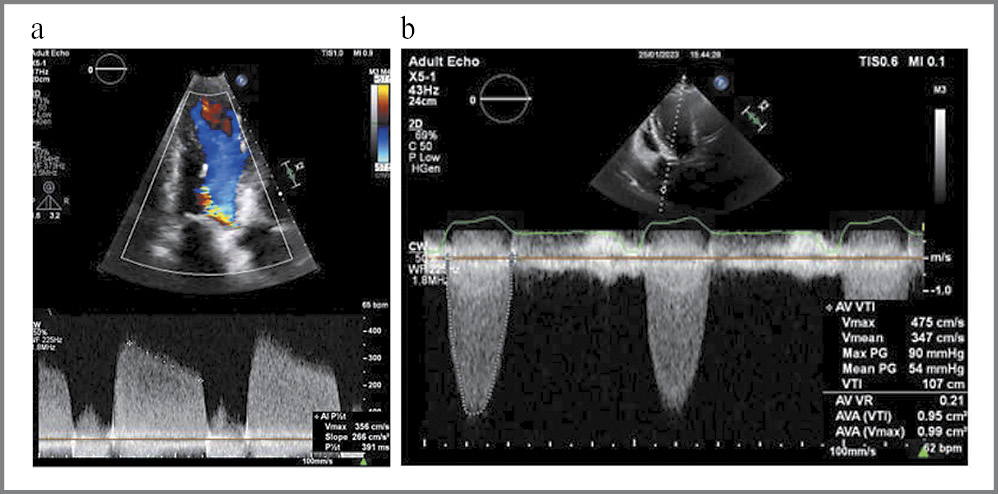

Вместе с этим выявлен стеноз устья аорты с максимальным систолическим градиентом давления на аортальном клапане (мГДсАК) 90 мм рт. ст., средним градиентом давления 54 мм рт. ст., площадью отверстия по уравнению непрерывности потока 0,9–1,0 см2, что соответствует тяжелой степени стеноза устья аорты. Также отмечалась аортальная регургитация (АР) 2–3-й степени (рис. 6).

Рис. 6. Трансторакальная ЭхоКГ. Время полуспада диастолического градиента на АК – слева и показатели стеноза устья аорты – справа.

Fig. 6. Transthoracic echocardiography. On the left: the half-life of the diastolic gradient on the AV; on the right: the indicators of aortic valve stenosis.

Основные ЭхоКГ-параметры представлены в табл. 1. Обращают на себя внимание значительное увеличение массы миокарда ЛЖ (ММЛЖ), расчетная величина индексированного значения – 243 г/м2. Диастолическая функция, несмотря на столь выраженную гипертрофию миокарда, нарушена по типу замедленной релаксации. По данным тканевой миокардиальной допплерографии Еml=8 см/с (N>10 см/с), Ems=6,3 см/с (N >7 см/с), E/Em=16–17.